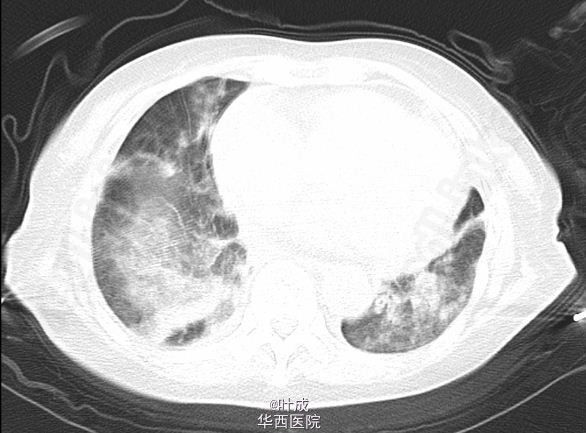

患者女,80岁,因“腹胀、呕吐1-天”入院。呕吐10+次,伴背痛。既往发现血压升高10年,最高180/100mmHg,药物控制一般;发现血肌酐升高3年,目前行规律血液透析(biw)。入院查体T:36.5oC,P:85次/分,R:22次/分,BP:186/76mmHg。神志清楚,心界向左扩大,心律齐。双肺呼吸音粗,散在湿罗音。全腹软,无明显压痛及反跳痛,腹部未触及包块。双下肢轻度水肿。辅助检查:血常规:Hb 109 g/L,WBC 12.51 10^9/L,N 10.65 10^9/L;血生化:ALT 61 IU/L,AST 239 IU/L,肌酐 585.0 umol/L,淀粉酶 428 IU/L,脂肪酶 998 IU/L,胆红素、电解质未见异常;心肌标志物示:肌钙蛋白-T 82.1 ng/L,尿钠素 >35000 pg/ml。CT示:胆囊炎,胰腺形态改变,胰周渗出,双肺散在条索、斑片、磨玻璃影及实变影,双侧胸膜增厚,双侧胸腔少量积液,心脏长大,心包少量积液(图1-2)。 入院诊断:1、急性胰腺炎(中度 原因?) 2、高血压病III级 极高危组 心脏长大 3、慢性肾功能不全(尿毒症期) 4、肺部感染 5、胆囊炎。 患者入院时一般情况可,于当日夜间感心累、气紧,拒绝面罩吸氧,后突发呼吸、心跳骤停,立即行胸外心脏按压,予血管活性药物及呼吸兴奋剂,请麻醉科会诊行气管插管有创呼吸机辅助通气,予镇静、镇痛、控制血压、纠正酸碱失衡等对症处理。患者恢复窦性心律,镇静下有创呼吸机人机配合可。反复沟通后,患者家属拒绝转ICU并签字。住院期间患者无尿,检测血气分析示氧合可,代谢性酸中毒逐步加重,血钾、血钠、血肌酐逐渐升高,住院第14天家属签字拔除气管插管,40分钟后患者临床死亡。部分实验室检查结果见下图。